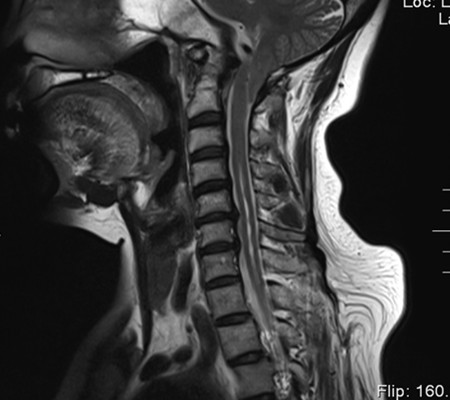

患者,女,53歲,以“頸肩部麻木、疼痛10月”入住神經外科一病區。該患者小腦扁桃體下疝畸形,頸椎先天發育也有異常。

主任劉增強、責任總醫師巨濤等人就此病例進行了多次討論。術前第一次運用先進的3D打印技術重塑了患者的寰枕部骨質及血管,證實了患者先天性寰椎后弓缺如。經過充分的術前準備,顯微鏡下切除了下疝的小腦扁桃體,結合3D打印結果,歷時4小時完成了我院第一例后路減壓+枕頸內固定術?;颊咝g后3天下床活動,10天出院。

寰枕畸形是指枕骨底部及第一、二頸椎先天發育異常,除以骨骼為主的發育異常外,還合并有神經系統和軟組織發育異常,包括扁平顱底、顱底陷入、寰枕融合、頸椎分節不全、寰樞椎脫位、小腦扁桃體下疝畸形等。